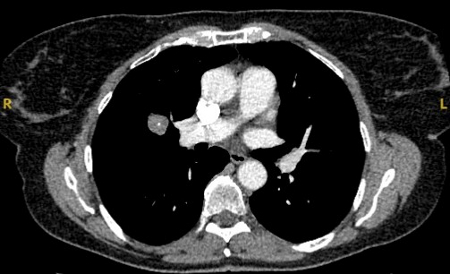

Tomografia computadorizada (TC) mostrando duas áreas (círculos vermelhos) de impactação mucoide dos brônquios subsegmentares do lobo superior esquerdo, resultando em aparência que mimetiza um nódulo

Do acervo de Dr. George Tsaknis, MD, PhD, FRCP (Londres), MRQA, MAcadMEd, PGCert; usado com permissão